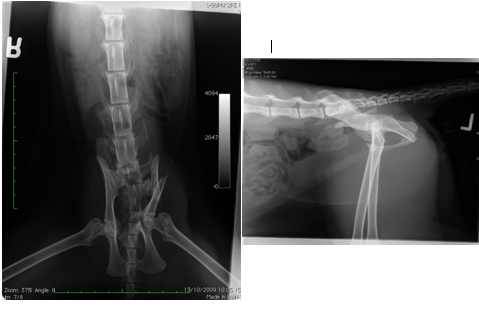

What is wrong with this cats radiograph?

You opt for surgical repair of the fracture.

Conservative treatment is cheap and non-invasive. Cats are often very painful and the outcome may be less predictable. In this case, both left and right hind limbs are affected, so the cat has lost both weight-bearing axes and therefore conservative management is not a good option